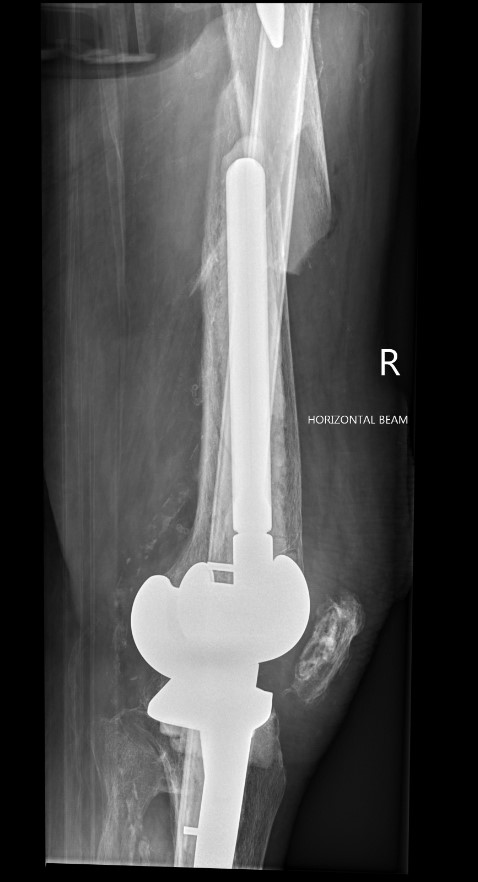

Long stem uncemented revision

Long stem uncemented revision with cortical strut allograft

Long stem uncemented revision with plate + cortical struts